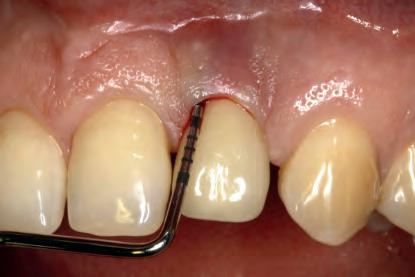

MANAGEMENT OF PERI-IMPLANTITIS IN THE AESTHETIC ZONE

The management of peri-implantitis cases in aesthetically demanding areas is a highly relevant clinical challenge due to the increased risk of mucosal recessions subsequent to the treatment. The exposure of the implant surface may result in an aesthetically unacceptable outcome. Thus, the additional goal of peri-implantitis management in aesthetic areas is the preservation of the esthetics.

The lecture will elaborate on the remodeling process that peri-implant tissue undergoes following the surgical peri-implantitis treatment. It will further address the step-by-step surgical treatment protocol for the management of peri-implantitis cases in the aesthetic zone and the rationale for soft-tissue grafting as part of the treatment protocol. Clinical scenarios resulting in unacceptable aesthetic outcomes requiring implant removal and the “second-round” implant planning will be further discussed.